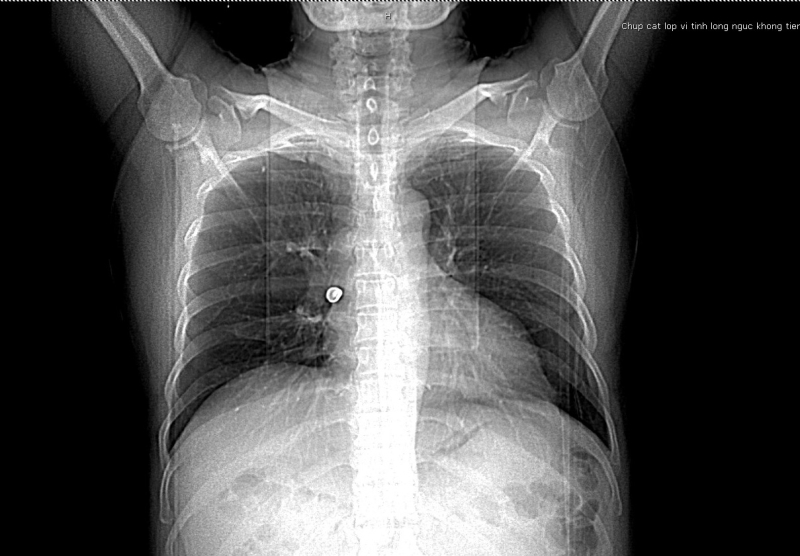

Trước nhập viện bệnh nhân bị ho sặc, tức ngực, khó thở. Tại Bệnh viện Bãi Cháy, bệnh nhân được thăm khám lâm sàng, thực hiện các xét nghiệm, chẩn đoán hình ảnh. Kết quả chụp CT scanner lồng ngực phát hiện vị trí phế quản phải có hình ảnh dị vật phản quang kích thước 17x12mmm. Các bác sĩ đã hội chẩn chuyên khoa hô hấp và chỉ định can thiệp nội soi phế quản để gắp dị vật.